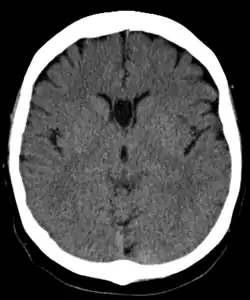

- Mypacs scan by Rolando Reyna, Radiologist, Hospital Santo Tomas, Panama. Good image, but text is incorrect and not referenced.